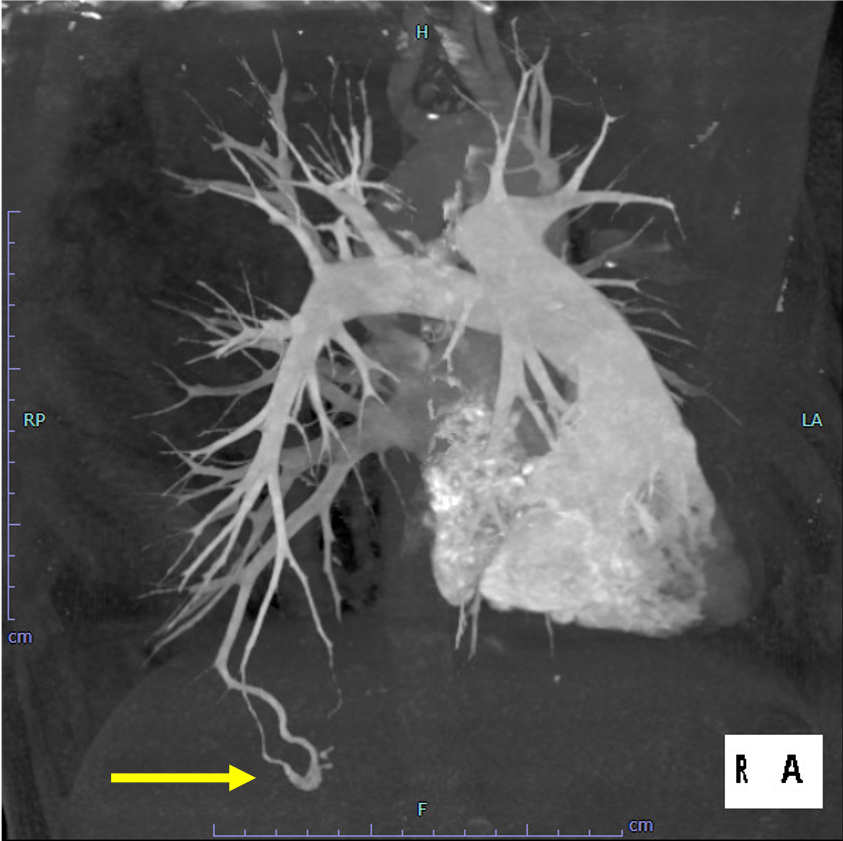

尿路の精査目的で施行した単純CTで, 偶発的に右肺下葉に肺動静脈奇形を認めた. 症状はなく, 流入動脈径は細径であったが, 今後, 脳梗塞などの神経学的合併症を引き起こす可能性があることから, 血管塞栓術の方針となった. 治療方針決定のため, 造影CTを施行した. 造影CTを参照して血管造影, コイル塞栓術を施行し, 良好な治療効果が得られた.

肺動静脈瘻の評価として検査依頼を受けたため、固定法により肺動脈相と肺動静脈相での撮影を行った。治療の一助となるよう肺動静脈相より肺動脈相をサブトラクションし肺動脈、肺静脈を色分けし3D作成を行った。

当該疾患の診断における造影CTの役割

肺動静脈奇形(肺動静脈瘻)の塞栓術の重要性は近年高くなっており, 術前造影CTでの解剖学的評価, 治療戦略が重要である. 従来は3mm以上の流入動脈をもつ肺動静脈奇形が塞栓術の適応とされていたが, 3mm以下の小さな流入動脈をもつ肺動静脈奇形でも重篤な脳神経合併症を起こすことがあり, 現在は流入動脈のサイズに関わらず治療適応と考えられている1-2).

肺動脈は体動脈よりも壁のコンプライアンスが高いため伸縮しやすく, また肺動脈内では線溶系が亢進しているため血栓が溶解されやすい状態とされる. そのため肺動静脈奇形では塞栓術後の再発率が高いことが報告されており, 再発を予防するためには適切なコイルサイズ, 十分な量のコイルを使用するtight packingが必要である. 肺動静脈奇形では複数の流入動脈を有するものも少なくなく, 術前CTにて流入動脈の解剖を十分検討することが重要である.

CT技術や撮像プロトコル設定について